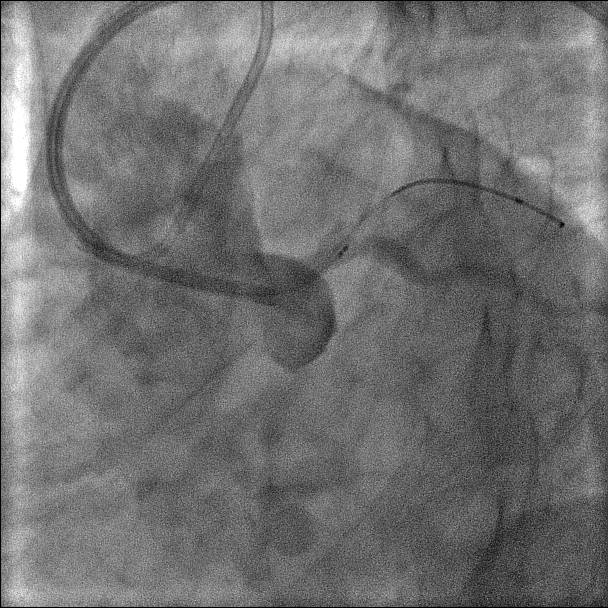

Final result